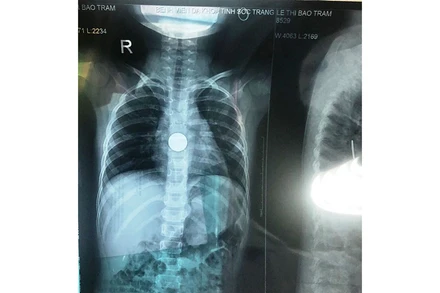

Ngày 3-3, Khoa Tai Mũi Họng - Bệnh viện đa khoa tỉnh Sóc Trăng vừa gắp thành công dị vật (đồng xu) cho bé gái L.T.B.T (6 tuổi), ngụ tại xã Đại Ân 2, huyện Trần Đề, tỉnh Sóc Trăng.